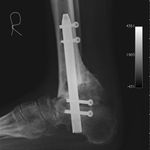

Because of his diabetic and vascular condition, one of the options given to him was amputation. He is a motivational speaker and it would have seriously affected his functioning. He sought our advice and he was told that the option of amputation was viable but we would recommend an arthrodesis of the ankle using an intra-medullary device (BIOMET -http://www.biomet.com/regions/caribbean/trinidadAndTobago.cfm) which we have previously utilized to good effect in cases like these.

He opted to have a right hind foot arthrodesis, which was carried out utilizing an intramedullary arthrodesis nail, which was performed in July 2011.